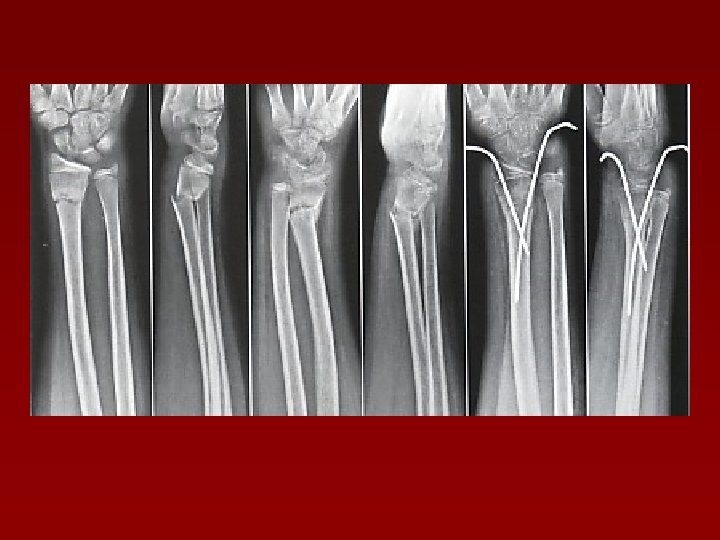

Tratament ortopedic – indicaţii: Fracturi simple, fără/cu moderată deplasare n Fracturi cu traiect transversal, stabile după reducere n Fracturile foarte cominutive cu deplasare n Aparat gipsat brahio-palmar, cotul la 90º, mâna în supinaţie ! Rtg săptămânal, în primele 4 săptămâni !

Fractură 1/3 distală radius redusă ortopedic + imobilizare în aparat gipsat

Tratamentul chirurgical – indicaţii: n Fracturi instabile n După 7 -10 zile de tratament ortopedic n După redeplasarea fragmentelor după tratament ortopedic n Fractura în cadrul unor polifracturi n Fractura deschisă n Fractura cu compresie vasculară

Reducere chirurgicală şi OS cu placă şi şuruburi Fractura 1/3 medie AO antebraţ + fractura epifizei distale radius Aspect la 2 ani postoperator

Reducere- OS cu DCP şi şuruburi